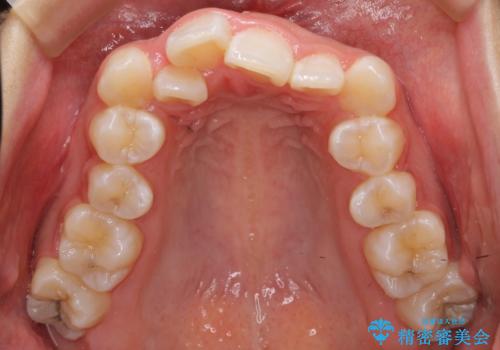

上の歯並びが前にずれて、さらに前歯が内側に倒れて過蓋咬合を呈していました。

奥歯のかみ合わせもずれていたため、上の奥歯を後ろに下げる処置をミニスクリューを用いて行いました。